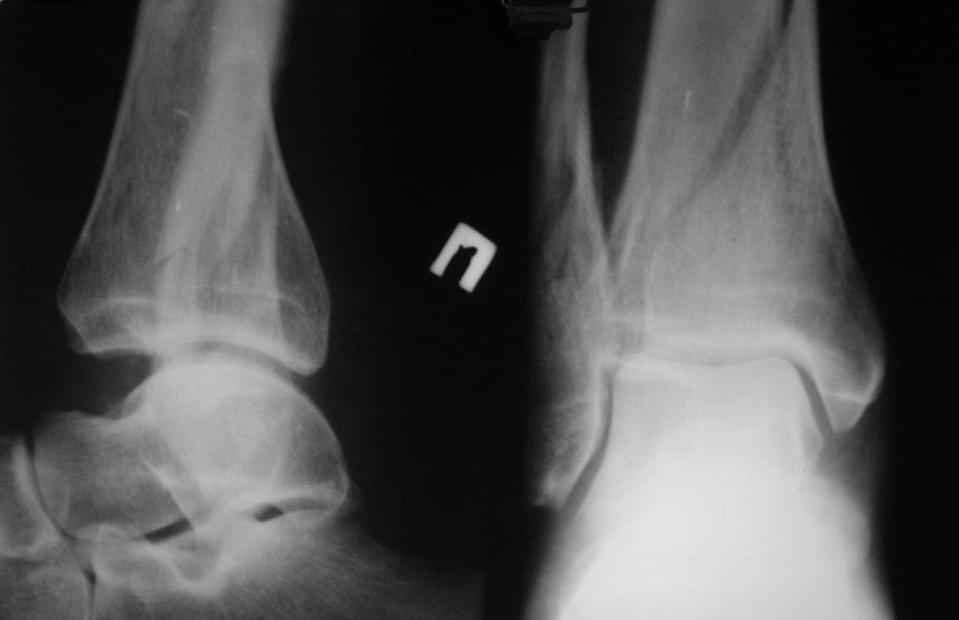

перелом пилона. тактика лечения

помогите определиться с тактикой лечения даного перелома пилона

Больной, 46 лет. Травма 27.08.08. При поступлении, в травмпункте была проведена блокада места перелома, иммобилизация гипсовой повязкой. Единого мнения по поводу дальнейшего лечения пока нет. Просьба высловиться по поводу возможностей лечения даного перелома, вообще возможности оперативного лечения. Спасибо за ответы.

прошу прощения за то, что забыл приложить снимки

открытая репозиция и фиксация

- малоберцовая - 3.5 мм 1\3 трубчатая пластина.

- большеберцовая - масса вариантов, начиная с множественных шурупов без пластины и заканчивая locking plate для дистальной тибии